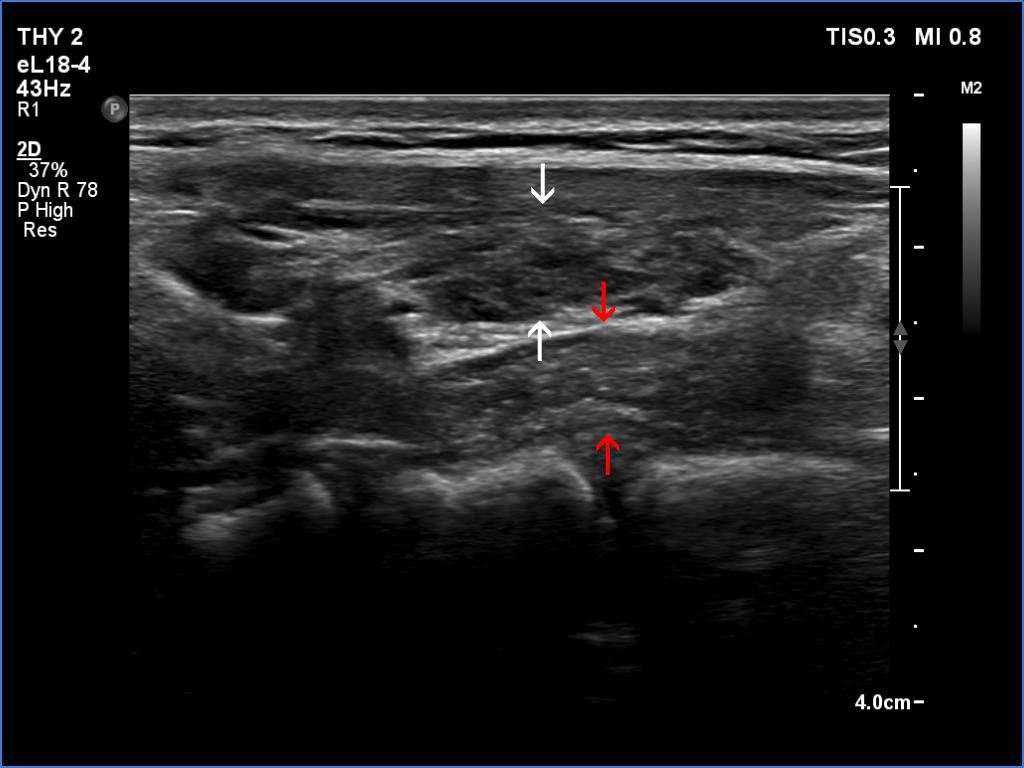

Lymphocytic thyroiditis - case 445 (ultrasonographic picture 4b)

Left lobe, longitudinal scan. Note that the depth of the thyroid (the distance between the white arrows) does not exceed that of the esophagus (the distance between the red arrows).